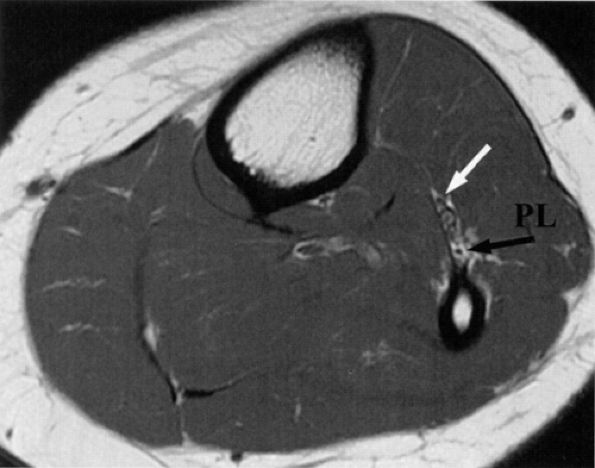

FIGURE 6.28 ● The normal peroneal nerves. Axial PD-weighted image of the proximal leg depicting the deep (white arrow) and superficial (black arrow) peroneal nerves, deep to the peroneus longus muscle (PL).

It is sometimes difficult to appreciate the common peroneal nerve and its branches as they travel around the fibular neck. The two branches are better seen as they dive underneath the peroneus longus muscle. In older or heavy patients, the peroneus longus muscle is less bulky and a fat plane is identified between the muscle and adjacent fibula (Fig. 6.28).